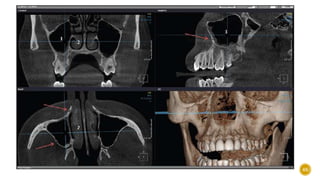

ZONE 1

 Also known as the “traumatic zone”

 1. BONE

 Part of the anterior maxilla is a protruding alveolar

process with thin labial and thick palatal cortical plates

covering and protecting upper front teeth.

 Evaluate the deficiency